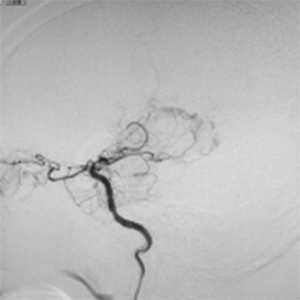

程度が軽い場合には、薬の治療(内科治療)のみを行います。程度が軽い方は、お薬だけで脳梗塞の再発を防げる場合も多いです。しかし、程度がひどい場合、脳血流が低下している場合には、お薬だけでは、2年で20%前後の人が脳梗塞の再発を起こすともいわれております。狭窄や閉塞は慢性的に詰まっており、再開通させることはできません。そのかわりに、頭皮の血管(主に、浅側頭動脈)を剥離し、頭の中の脳血管に顕微鏡を用い吻合することにより、脳の血流量を外から増やすバイパス手術を行います。浅側頭動脈中大脳動脈バイパス術(STAMCAバイパス術)といいます。バイパス術で脳の血流を増やすことにより、脳梗塞の再発する危険性を大きく減らすことできます。現在のガイドラインで推奨されている手術適応は、簡単にいうと73歳以下の比較的元気な方で、脳の血流が著しく低下している方です。最近は、平均寿命も延び、高齢な元気な方も増えております。国内、海外でも高齢者に対するバイパス手術で良好な成績を示す報告は増えております。当院でも、全身状態やほかのご病気の有無を確認し、全身状態が良い場合には、高齢者でも、十分な術前検査を行ったうえで、バイパス手術を行っており、良好な成績を出しております。

閉塞した脳血管